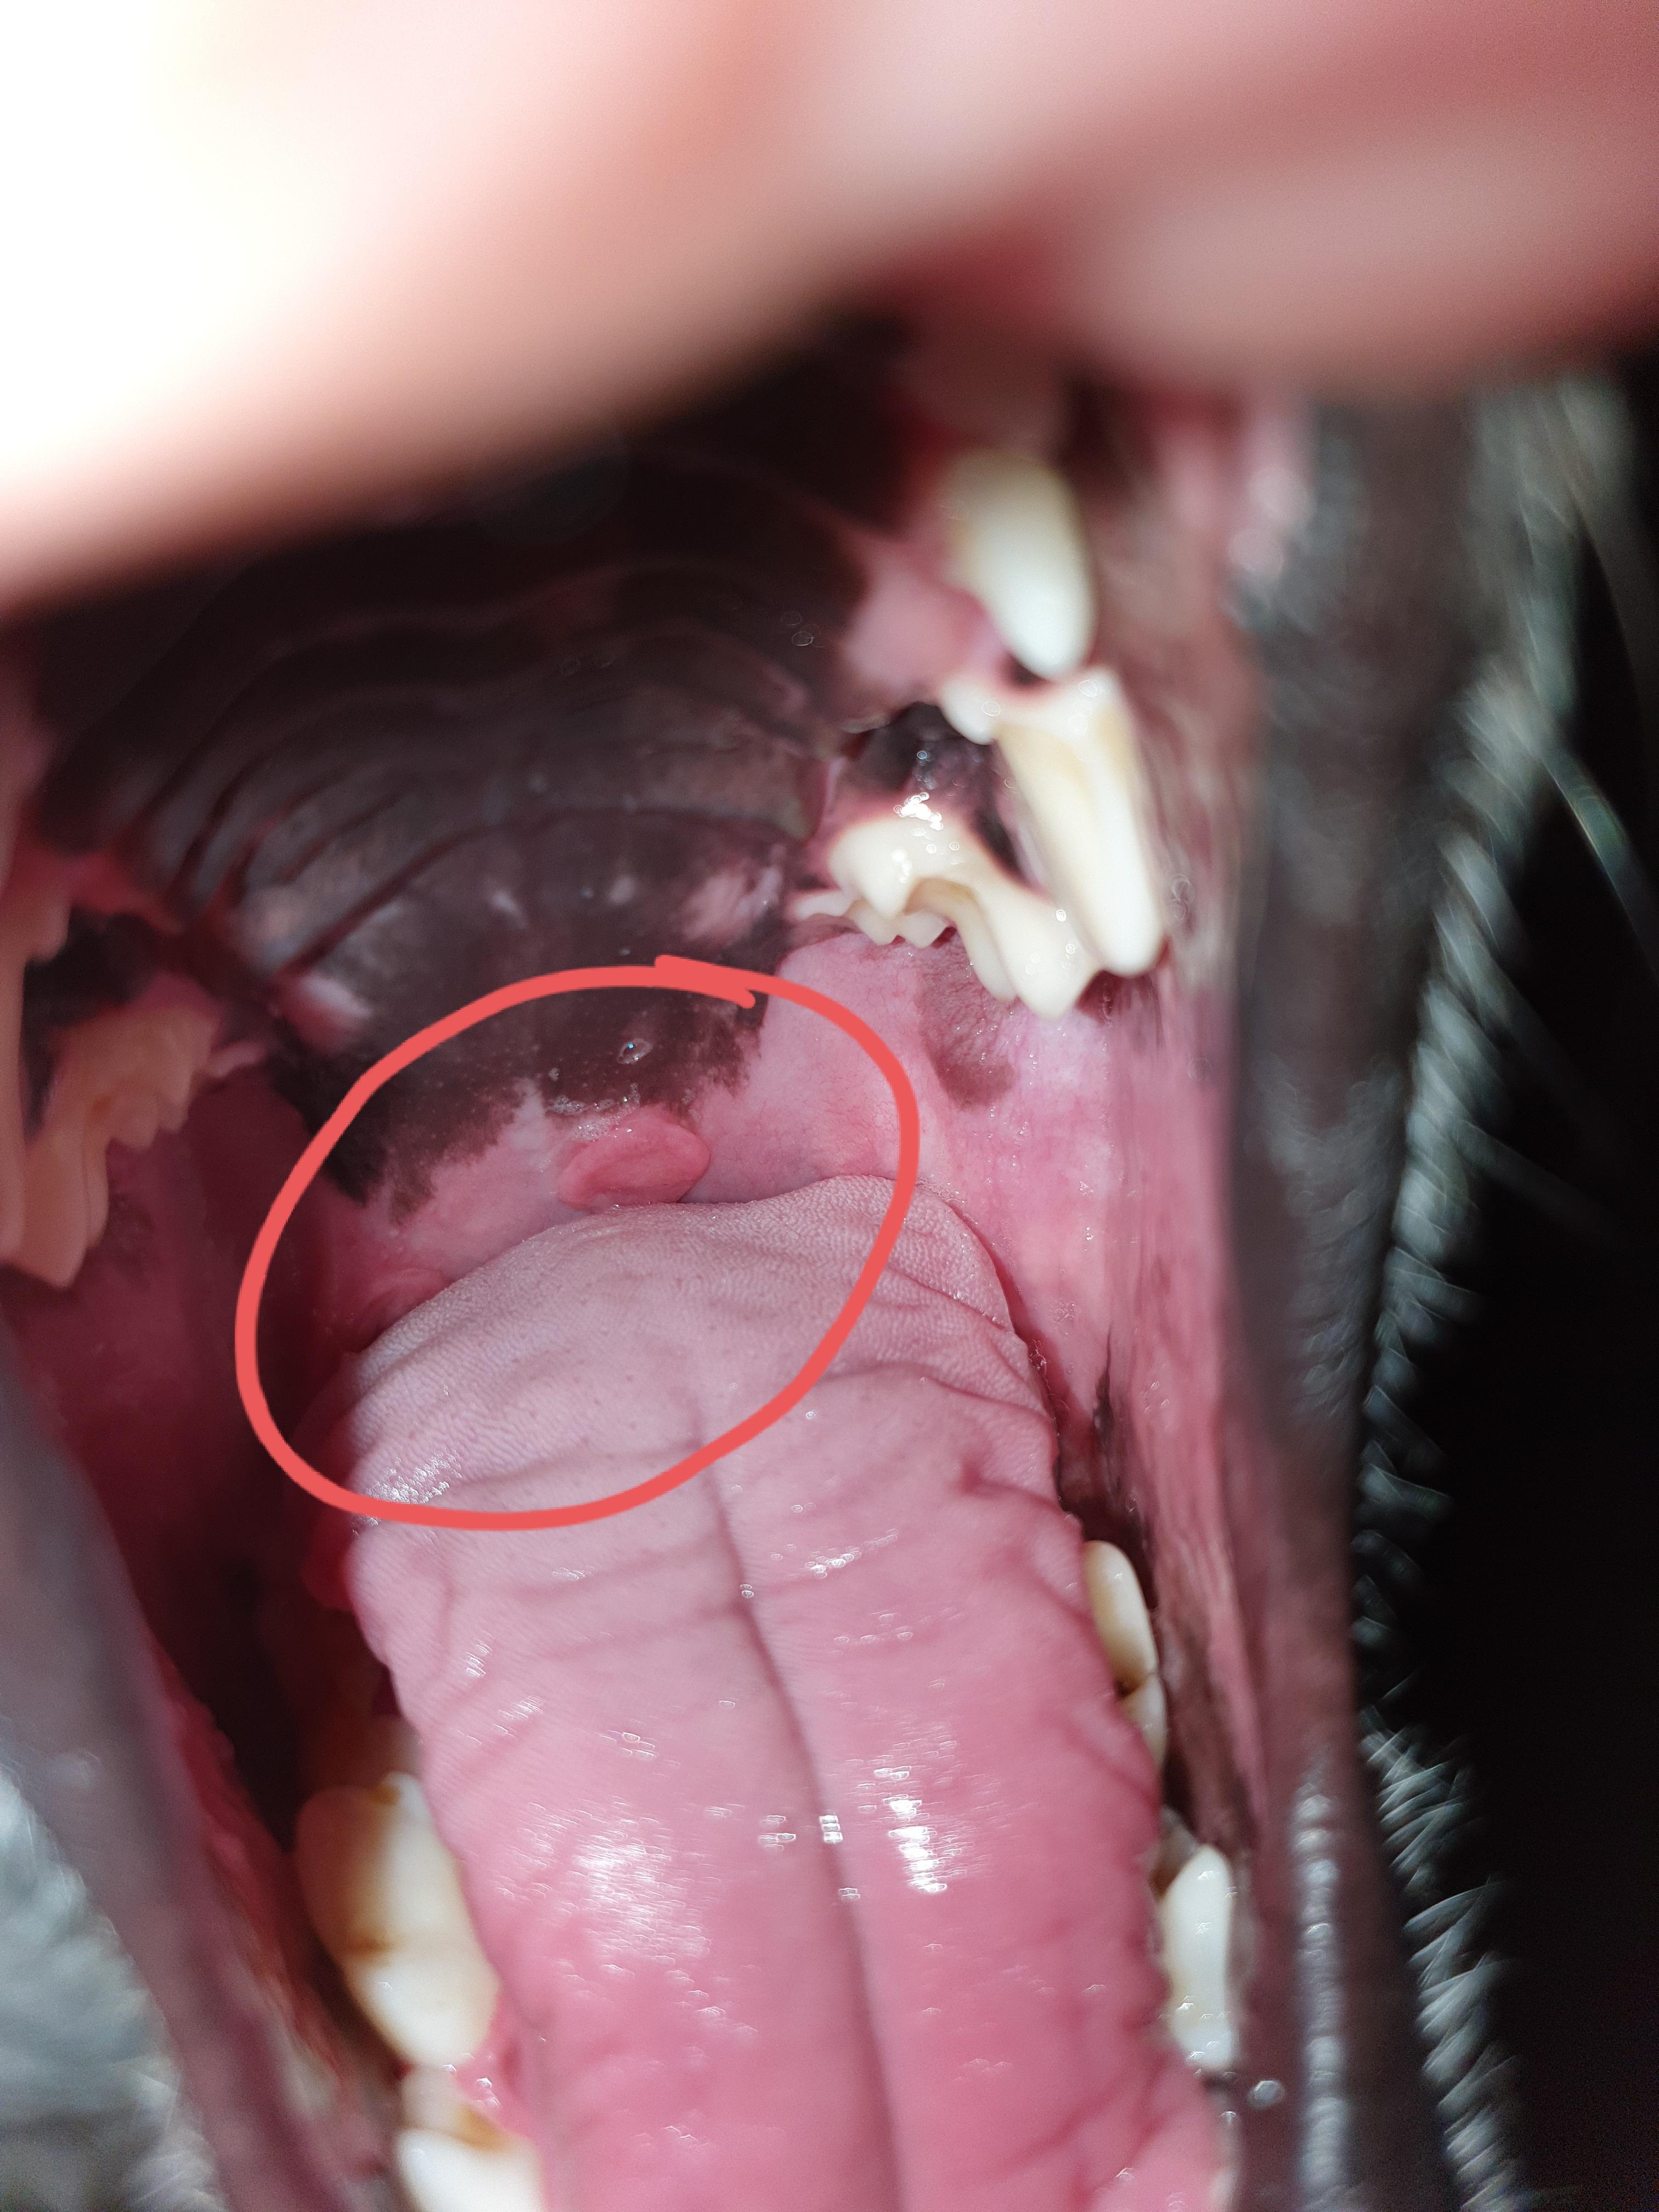

Was Hat Der Hund Am Gaumen? (Gesundheit Und Medizin, Tiere)

hund gaumen.